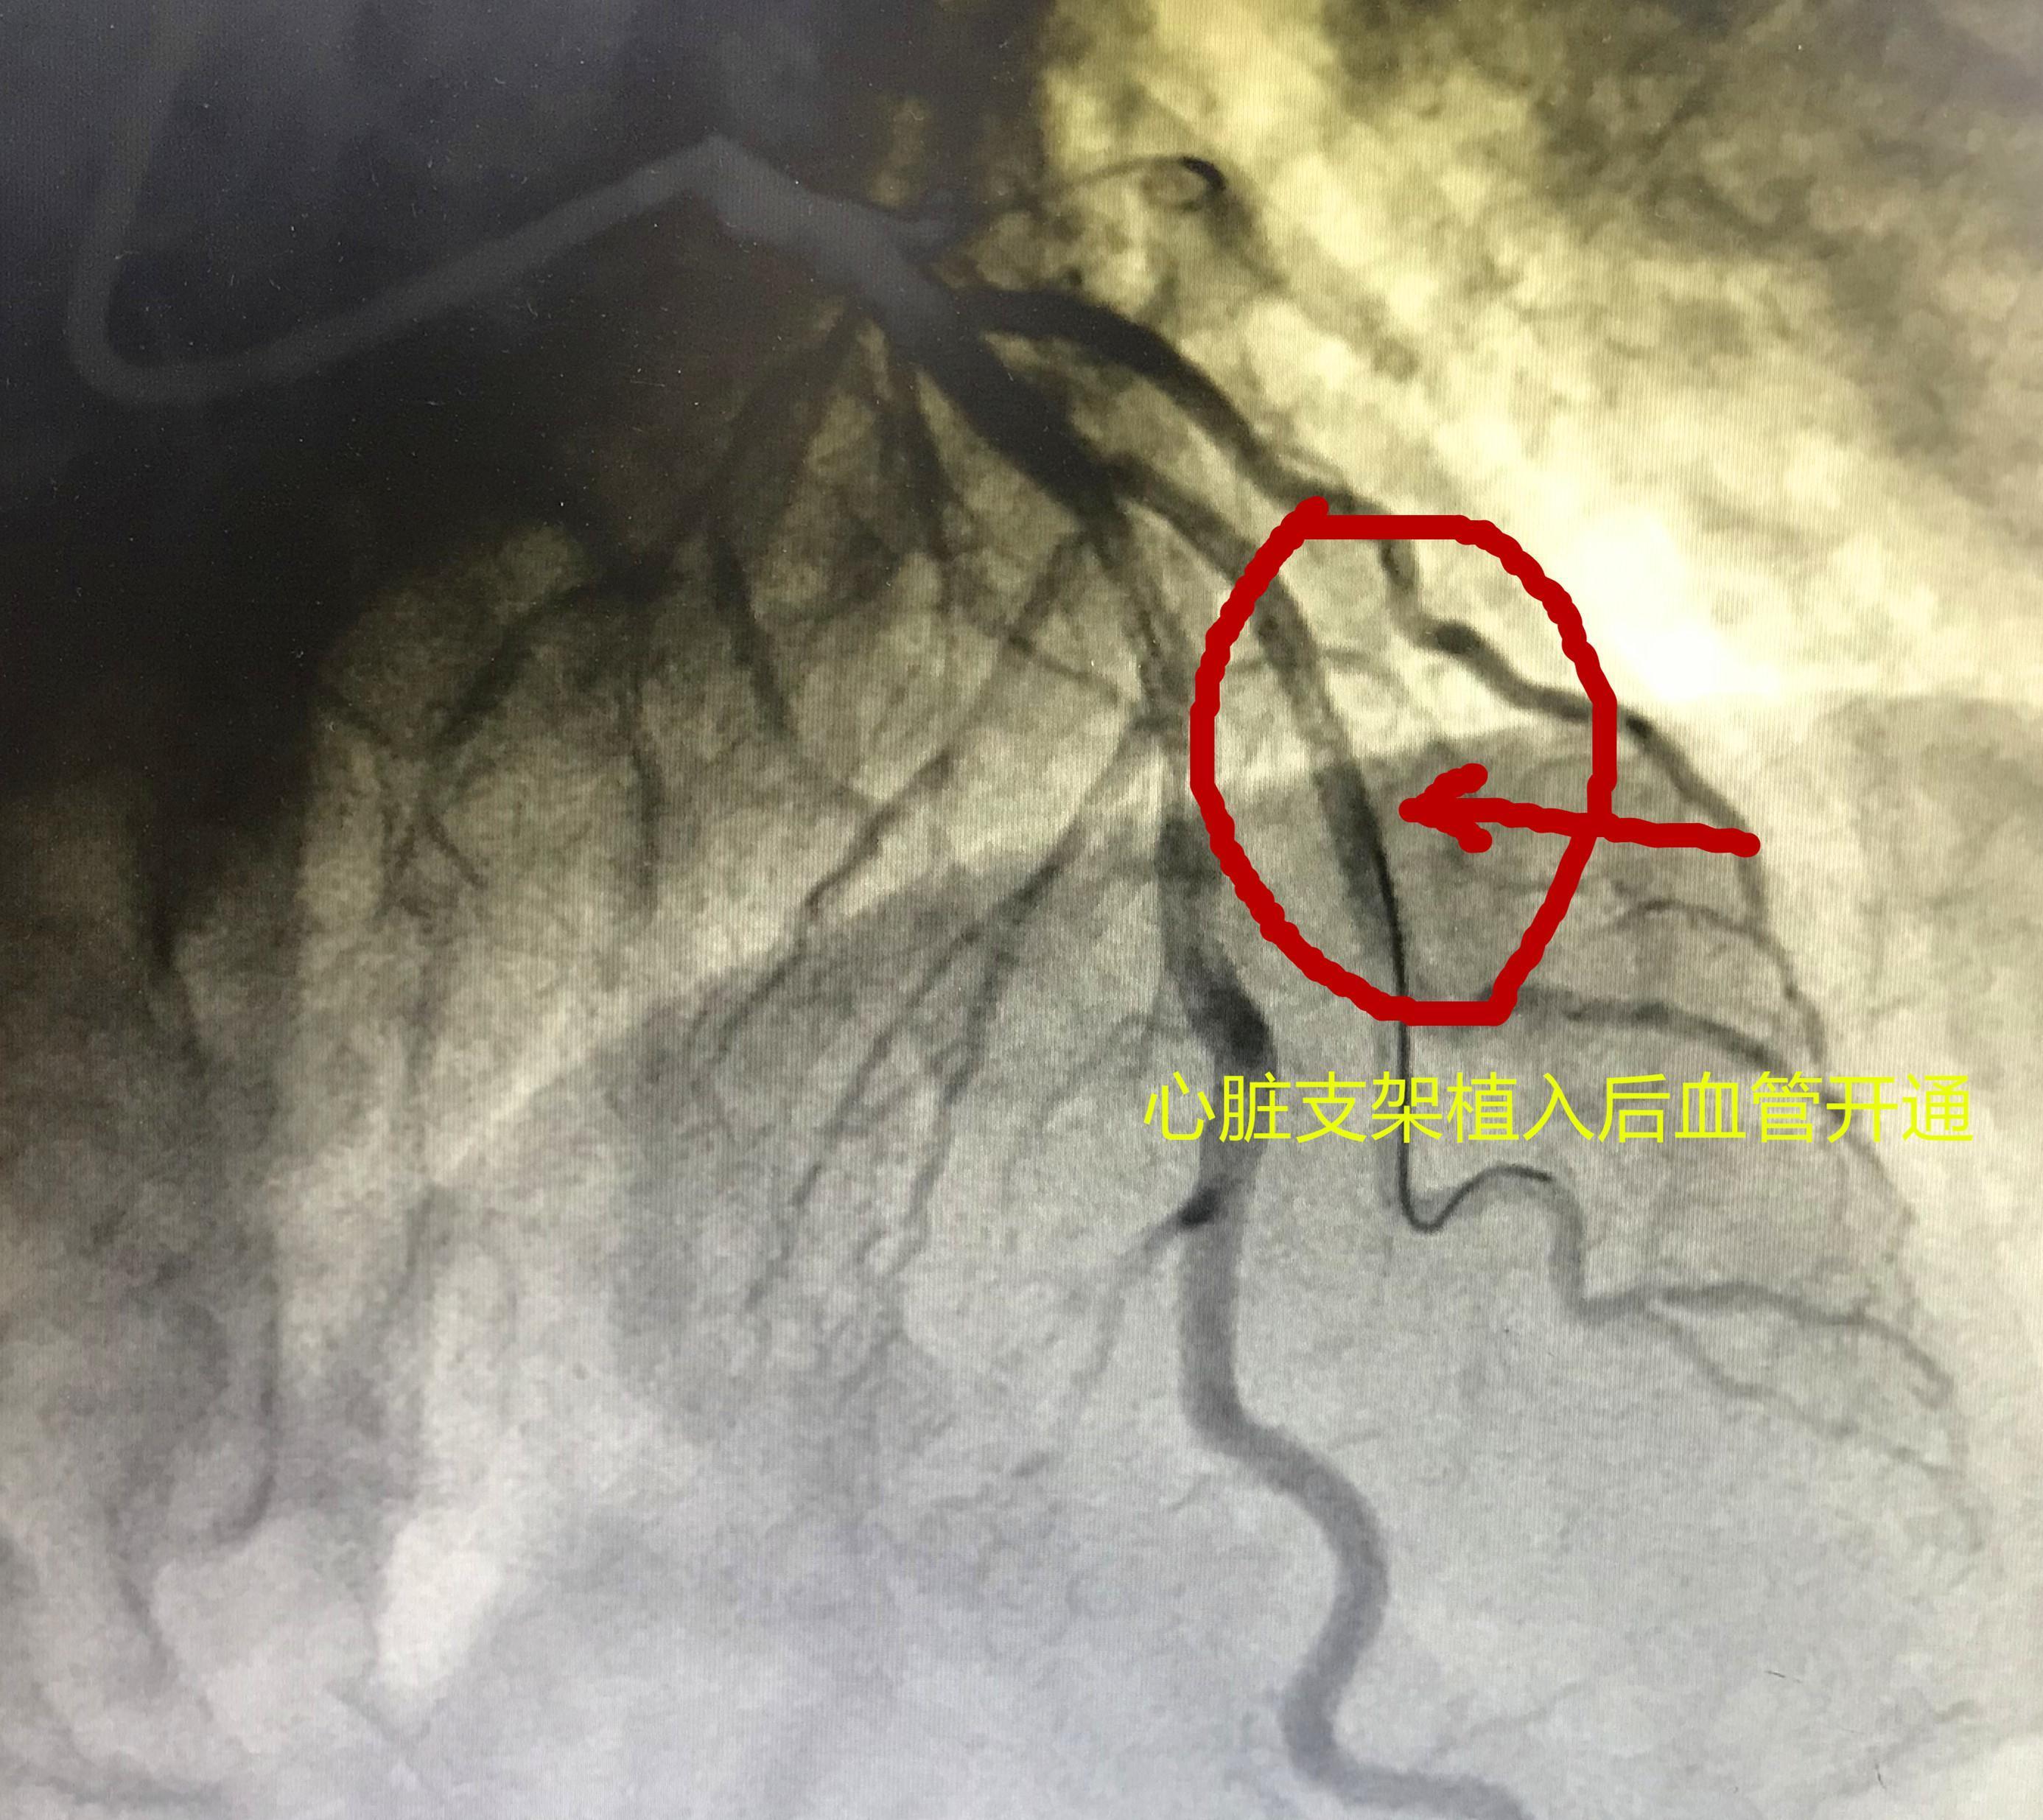

老人先是感觉心率火辣辣地闷一阵,很快就恢复正常了,手术结束才半小时,自觉心里舒服多了,心绞痛症状消失了!

文章插图

心脏支架植入以后血管完全恢复

这是一例效果比较完美的病例,老人症状恢复快,和准确诊断,精准治疗有直接关系。